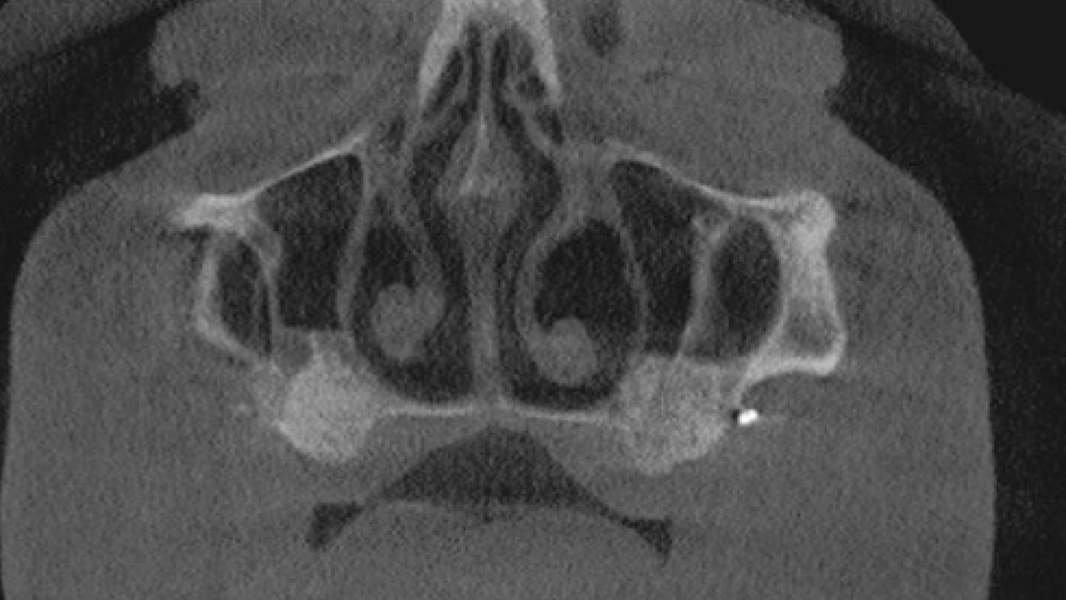

Die rein spongiösen Granulate ermöglichen durch eine zügige Remodellierung einen schnellen Knochenaufbau bei eingegrenzten Defekten, wohingegen das kortiko-spongiöse Material beim Aufbau ausgeprägter knöcherner Defekte für eine längere Volumenstabilität sorgt.

- Die schnelle Remodellierung von MinerOss A verkürzt die Wiedereingliederungszeit und ermöglicht die Implantation nach 3–4 Monaten.9, 10